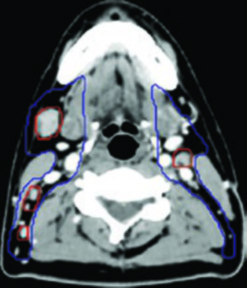

En el cuello, el CTV70 corresponde al GTV ganglionar más 3 a 5 mm. Los ganglios pequeños que son claramente patológicos pero de menor volumen pueden tratarse a dosis intermedias de 63 a 66 Gy.

En el cuello, el CTV54-56 incluye los ganglios retrofaríngeos bilaterales y los niveles ganglionares IB a V bilateralmente. El nivel IB puede omitirse en pacientes N0 sin extensión hacia la cavidad oral. El cuello bajo puede excluirse en pacientes N0 seleccionados. Estas consideraciones comparten principios con la delineación descrita para el cáncer de laringe.

Un aspecto que merece atención especial es el nivel V cervical. En tumores avanzados (N2-N3), la cobertura del nivel V hasta la grasa posterior a la clavícula es imprescindible. La omisión de este nivel puede conducir a recurrencias marginales de difícil rescate. De manera comparable, la cobertura ganglionar completa cobra relevancia en los tumores de hipofaringe.

Paciente con carcinoma nasofaríngeo no queratinizante, EBV positivo, estadio T1N1. La RM mostró un tumor confinado a la nasofaringe sin extensión parafaríngea significativa. La PET/CT confirmó un ganglio patológico en niveles II y III derechos. El GTV70 primario se limitó al tumor visible en la fusión TC-RM, con un CTV70 de expansión 3 mm. El CTV subclínico incluyó la nasofaringe completa, la mitad del seno esfenoidal, un tercio del clivus, la fosa pterigopalatina bilateral y los niveles ganglionares IB a V bilaterales con ganglios retrofaríngeos.

Paciente con enfermedad localmente avanzada, extensión intracraneal a través del foramen oval y seno cavernoso ipsilateral, adenopatías bilaterales en niveles II-V. El GTV70 incluyó el tumor primario con toda su extensión intracraneal visible en RM T1 con gadolinio, así como el conglomerado ganglionar necrótico. El CTV70 se expandió 5 mm en la mayoría de las direcciones, reduciéndose a 0 mm en la interfaz con el lóbulo temporal. El CTV subclínico requirió la inclusión del seno esfenoidal completo, el clivus completo, la cavidad de Meckel bilateral y todos los niveles cervicales bilaterales hasta la grasa posterior a la clavícula en el nivel V.

Ambos casos fueron tratados con quimiorradioterapia concurrente con cisplatino, esquema SIB en 33 fracciones (70 Gy al PTV70, 56 Gy al PTV56), con verificación mediante CBCT diario.